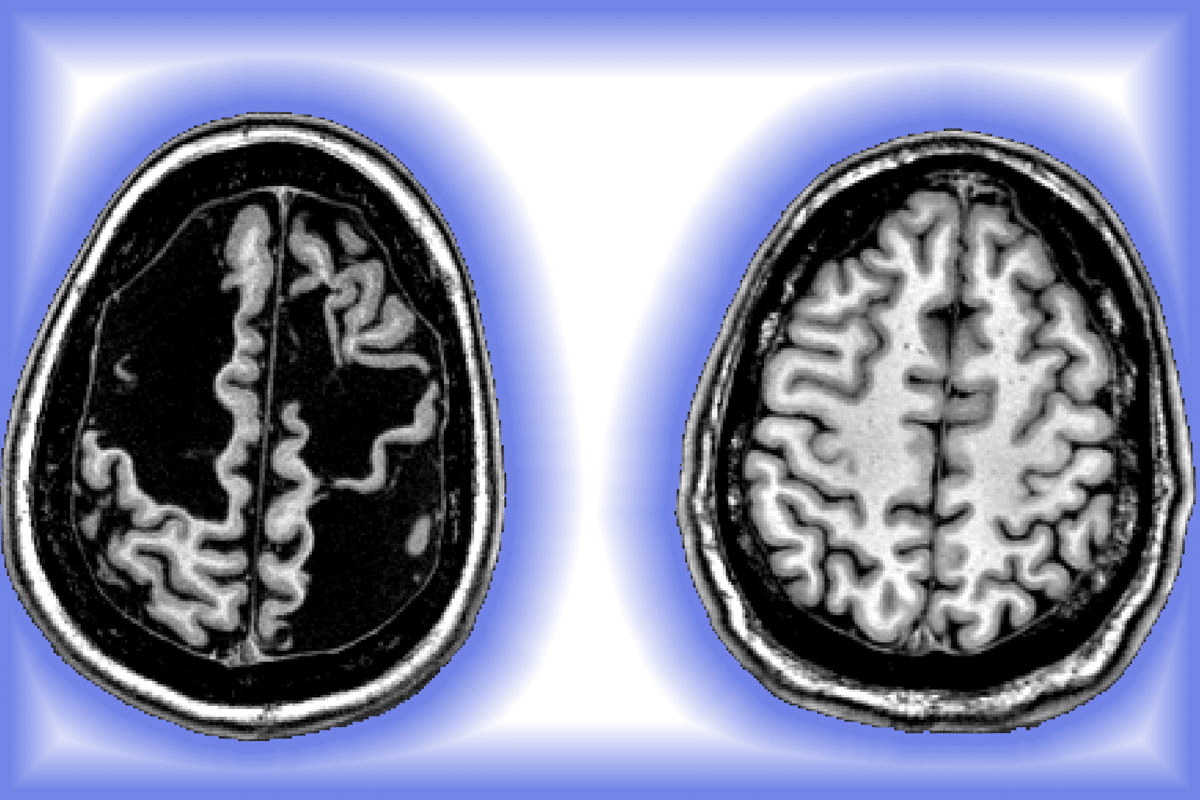

Normal Brain vs. TBI Brain: Understanding the Differences

It’s important to know how a normal brain differs from one with a Traumatic Brain Injury (TBI). TBI can change the brain’s structure and how it works. This leads to changes in thinking, feeling, and behavior.

Structural Changes

TBI can cause several changes in the brain’s structure, including:

- Bleeding: Hemorrhages can occur due to the rupture of blood vessels.

- Swelling: Edema can lead to increased intracranial pressure.

- Tearing of nerve fibers: Diffuse axonal injury can disrupt normal brain function.

These changes can greatly affect how the brain works. Doctors say, “The extent of structural damage often correlates with the severity of TBI symptoms.”

Functional Alterations

Functional changes after TBI are just as important as structural ones. These changes can impact:

- Cognitive processes: Attention, memory, and executive functions can be impaired.

- Emotional regulation: Mood swings, depression, and anxiety are common.

- Behavioral changes: Impulsivity and aggression can occur due to frontal lobe damage.

Understanding these changes is key to creating effective rehabilitation plans. Research shows, “Early intervention can significantly improve outcomes for individuals with TBI.”

By knowing the differences between a normal brain and a TBI brain, healthcare providers can tailor care. This improves the quality of care and support for each patient.